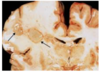

in the communicating form of the condition seen in the image, there is dilation of ___

in the communicating form of the condition seen in the image, there is dilation of ALL ventricles

the communicating form of the condition seen in the image can due to scarring/fibrosis of ____ or ____

the communicating form of the condition seen in the image can due to scarring or fibrosis of the arachnoid villi d/t tumors or infxns (TB, meningitis) or subarachnoid hemorrhage

the communicating form of the condition seen in the image is caused by reduced ____, such as in ____

the communicating form of the condition seen in the image is caused by reduced CSF resorption, such as in arachnoid fibrosis

the normal pressure form of the condition seen in the image is characterized by the triad of:

wet = urinary incontinence

wobbly = ataxia

the ex vacuo form of the condition seen in the image causes dilation of ____ due to ____ and causes a compensatory ____

the ex vacuo form of the condition seen in the image causes dilation of all ventricles due to cerebral atrophy and causes a compensatory increase in CSF

the non-communicating form of the condition seen in the image occurs between ____ & ____ or between ____ & _____

the non-communicating form of the condition seen in the image occurs between lateral & 3rd ventricle or between 3rd & 4th ventricle

the presentation of condition seen in the image in children is increased ____ because ____

the presentation of condition seen in the image in children is increased head circumference because skull bones (fontanelles & sutures) have not fused yet

the presentation of condition seen in the image in adults is increased ____

the presentation of condition seen in the image in adults is increased ICP

a complication of the condition seen in the image is ___ which is a triad of symptoms indicating an impending ____

a complication of the condition seen in the image is Cushing’s reflex which is a triad of symptoms indicating an impending herniation

• elevated systolic pressure (wide pulse pressure)

• bradycardia

• irregular respirations